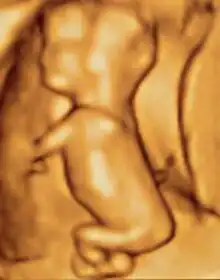

Modern 3D ultrasound images provide greater detail for prenatal diagnosis than the older 2D ultrasound technology.[6] While 3D is popular with parents desiring a prenatal photograph as a keepsake,[7] both 2D and 3D are discouraged by the FDA for non-medical use,[8] but there are no definitive studies linking ultrasound to any adverse medical effects.[9] The following 3D ultrasound images were taken at different stages of pregnancy:

- 3D Ultrasound of fetal movements at 12 weeks

75-mm fetus (about 14 weeks' gestational age)

Fetus at 17 weeks

Fetus at 20 weeks